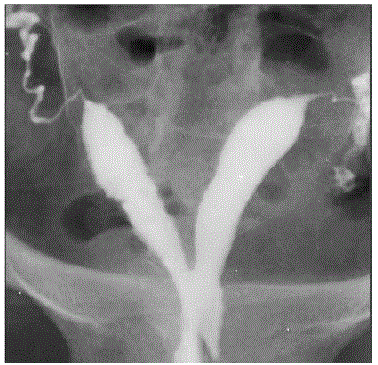

Veja a imagem abaixo e marque o diagnóstico.

https://www.google.com.br/search?q=hidrossalpinge+bilateral&source=lnms&tbm=isch&sa=X&ved=0ahUKEwj0_OioqbHaAhUBk5AKHWEzAksQ_AUICigB&biw=1024&bih=662#imgrc=a6s-NHneRkhrCM: